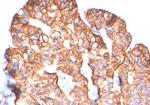

HER-2/c-erbB-2/neu/CD340 Antibody in Immunohistochemistry (Paraffin) (IHC (P))

免疫组化(石蜡) (IHC (P))

Assay-dependent